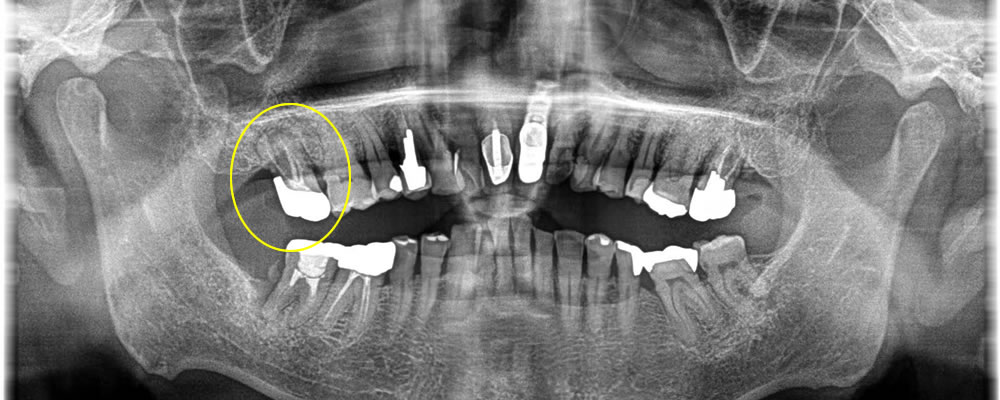

歯周病で歯を失った部分をインプラントで治療した症例

年齢

60代

性別

男性